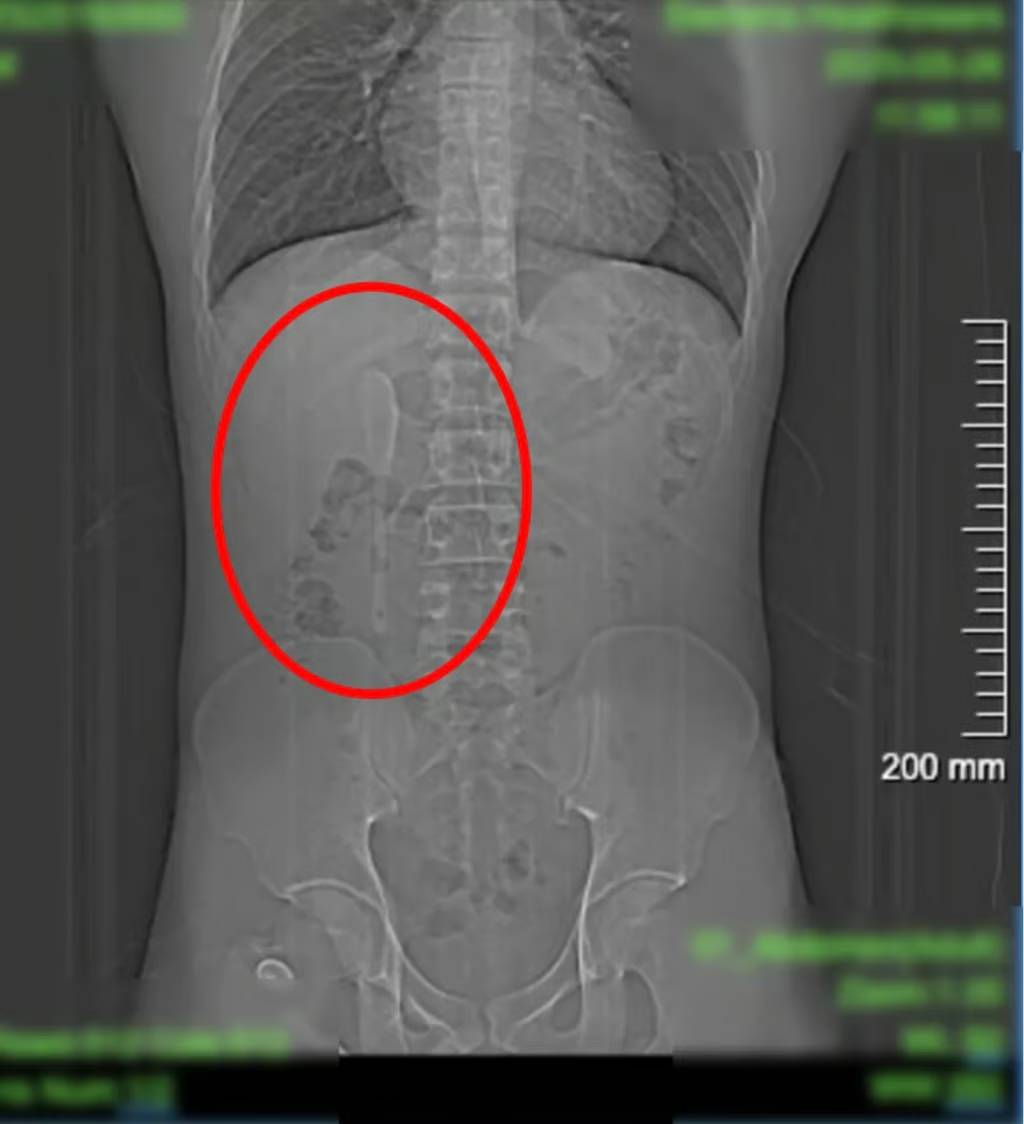

เมื่อวันที่ 28 มิถุนายน สำนักข่าว SCMP รายงานว่า ชายสกุลหยาน วัย 29 ปี ได้เข้าพบแพทย์ในนครเซี่ยงไฮ้ ประเทศจีน หลังจากที่เขาคิดว่าเขากลืนช้อนพลาสติกเข้าไปโดยไม่ได้ตั้งใจ ทว่าเมื่อแพทย์ตรวจสอบพบว่าเขาไม่ได้กลืนช้อนพลาสติกเข้าไป แต่เป็นช้อนยาว 15 เซนติเมตร

โดยช้อนติดอยู่ที่ลำไส้เล็กส่วนต้นซึ่งเป็นส่วนแรกของลำไส้เล็ก ช้อนอยู่ในตำแหน่งที่ไม่มั่นคง และทำให้การขยับเพียงเล็กน้อยก็อาจทำให้ลำไส้ทะลุ ทำให้เกิดการอักเสบหรือเลือดออกมาก